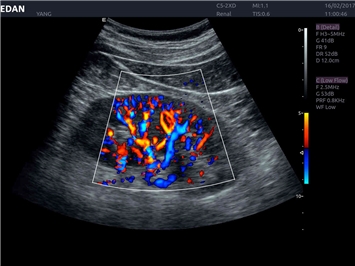

Трехмерная реконструкция ЦДК:

Да

Color 3D: